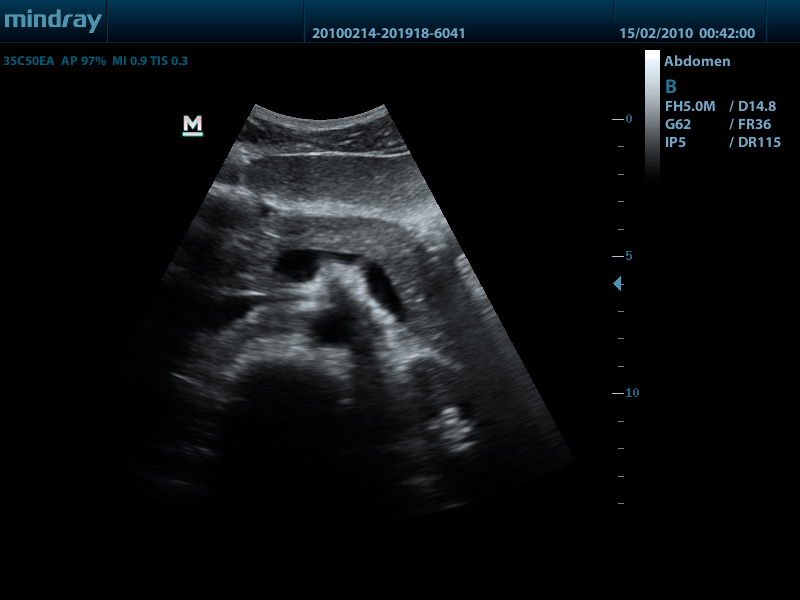

Конвексный датчик 35C50EA (2.0/3.5/4.5/5.0/Н5.0/Н6.0) R50

Mindray DP-50 – портативная цифровая ультразвуковая система с ЖК монитором 15 дюймов (1024Х768)

- диапазон сканируемых частот от 2,0 до 14,0 МГц

DP-50 – портативный УЗИ сканер разработан на базе новой платформы X-treme engine, используемой в хорошо зарекомендовавших себя цветных сканерах с доплером моделей DC-3, DC-7, DC-6. Эта платформа открывает возможности для расширений до уровня цветных сканеров и совместимости с широким диапазоном периферийного оборудования. X-treme означает интеллект, высокую скорость обработки данных, многоуровневую передачу сигналов, а также возможность оптимизации изображения и модульного расширения.

Область использования:

- у постели больного

- в полевых условиях

- в операционных